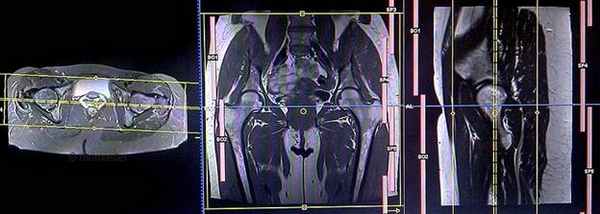

Серия Т1 vibe 3d с жироподавлением, коронарный срез 1мм, малое поле обзора (SFOV)

Планирование коронарных срезов на аксиальной плоскости; угловое расположение блока пересекает вертлужную впадину и головку бедренной кости пополам. Проверьте расположение блока на 2-х других плоскостях. Соответствующий угол должен быть получен в сагиттальной плоскости (рассекая головку бедренной кости и вертлужную впадину). Эти срезы должны полностью покрывать тазобедренные суставы, от седалищных бугров до уровня лобкового симфиза.